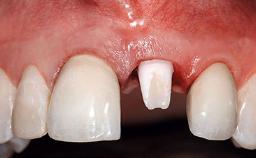

A 32-year-old female Caucasian patient with a compromised maxillary right central incisor was referred to us by a general dentist. Her chief complaints were discomfort and mobility of tooth 11 with unsatisfactory esthetics due to discoloration. The patient reported a previous trauma, some years earlier, as the origin of pathology on the afflicted tooth. Anamnesis was negative for any other dental or periodontal pathology in the remaining dentition. The patient did not take any medication and reported to be a light smoker (5–10 cigs/day). She had high esthetic expectations of her treatment. The extraoral examination revealed a high smile line with full exposure of her maxillary teeth and surrounding soft tissue in the area between the second premolars.

Lip Line No exposure of papillae Exposure of papillae Full exposure of mucosa margin

Periodontal Phenotype Low-scalloped, thick Medium-scalloped, medium-thick High-scalloped, thin